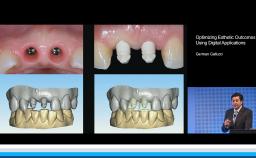

German Gallucci

My ITI - German Gallucci